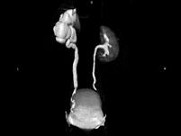

- 多项选择题女,42岁, 左侧腰背部胀痛不适1年余,5年前行左侧卵巢囊肿切除术, CT检查如图所示,下列说法正确的是 ( )

A、左侧附件区可见一囊性肿物,压迫输尿管下段

B、左侧输尿管下端狭窄

C、左侧肾盂肾盏扩张积水

D、左侧输尿管中上段扩张

E、考虑为左侧卵巢囊肿术后复发压迫并粘连输尿管致其狭窄